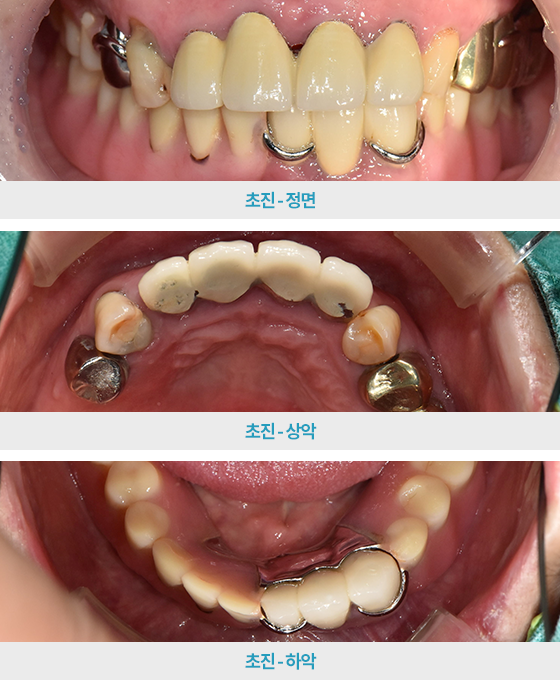

· 네비게이션 임플란트 / 상하악 식립 case

치료 후 사진

3~4개월 전 타치과에서 시술 마무리하였지만

불편한 곳이 또생겨 검진 진행한 케이스

하악 발치 진행 후 임시틀니 사용,

이후 임플란트 식립 2달 뒤 체결하며 최종 부분 틀니 완성

*환자분 비용부담 보험임플란트 2개,

보험틀니 활용하여 적은 비용으로 하악치료 완성